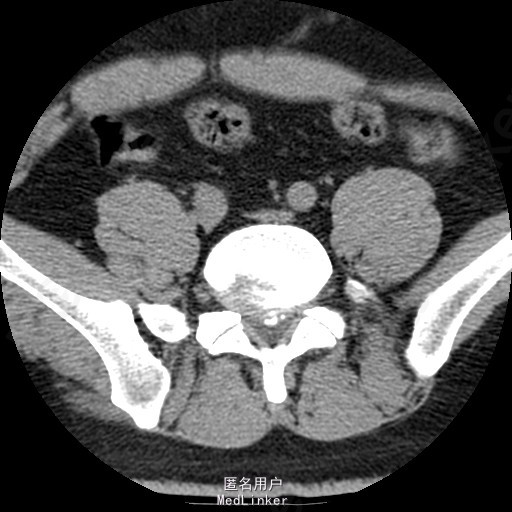

查体:腰部叩痛,腰部活动受限,左侧膝内侧、小腿外侧、内踝、足部感觉减退,右侧小腿、足背感觉减退,屈髋、伸膝、踝背伸肌肌力左侧4级,右侧4-5级,踇背伸、跖屈肌肌力左侧3-4级,右侧4级,双侧膝腱反射+,跟腱反射+,双侧巴氏征阴性,直腿抬高试验左侧40°阳性,右侧阴性。 辅助检查: X-ray:腰椎退行性变,多节段不稳 CT:腰椎间盘突出并椎管狭窄伴钙化,腰2-3,3-4,4-5,腰5骶1 MR:腰椎间盘突出并椎管狭窄,腰2-3,3-4,4-5,腰5骶1 上传受限无法全部上传,见谅

诊断:腰椎间盘突出症并椎管狭窄 处理: 1、完善相关辅助检查,明确诊断,有无手术指证; 2、完善手术评估,有无手术禁忌,手术风险及并发症; 3、在全麻下行腰椎后路多节段减压椎间植骨融合内固定术 4、腰2-3,腰3-4行开窗减压,腰4-5,腰5-骶1行椎间Cage植骨融合